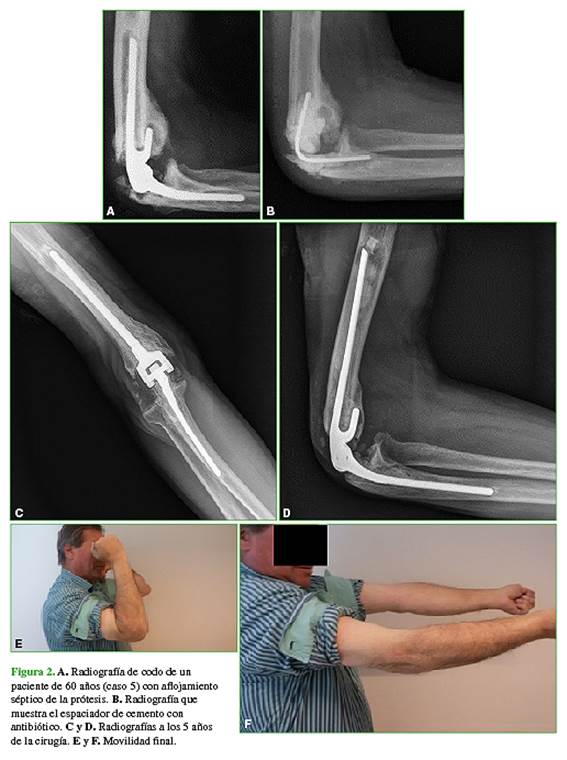

Al evaluar a los pacientes según su stock óseo, cinco fueron incluidos dentro del grupo A y cinco, dentro del grupo B (Figuras 2 y 3). El grupo A tenía menos cirugías previas y obtuvo mejores resultados funcionales, principalmente en la recuperación de la fuerza de extensión, que el grupo B (Tabla 3).